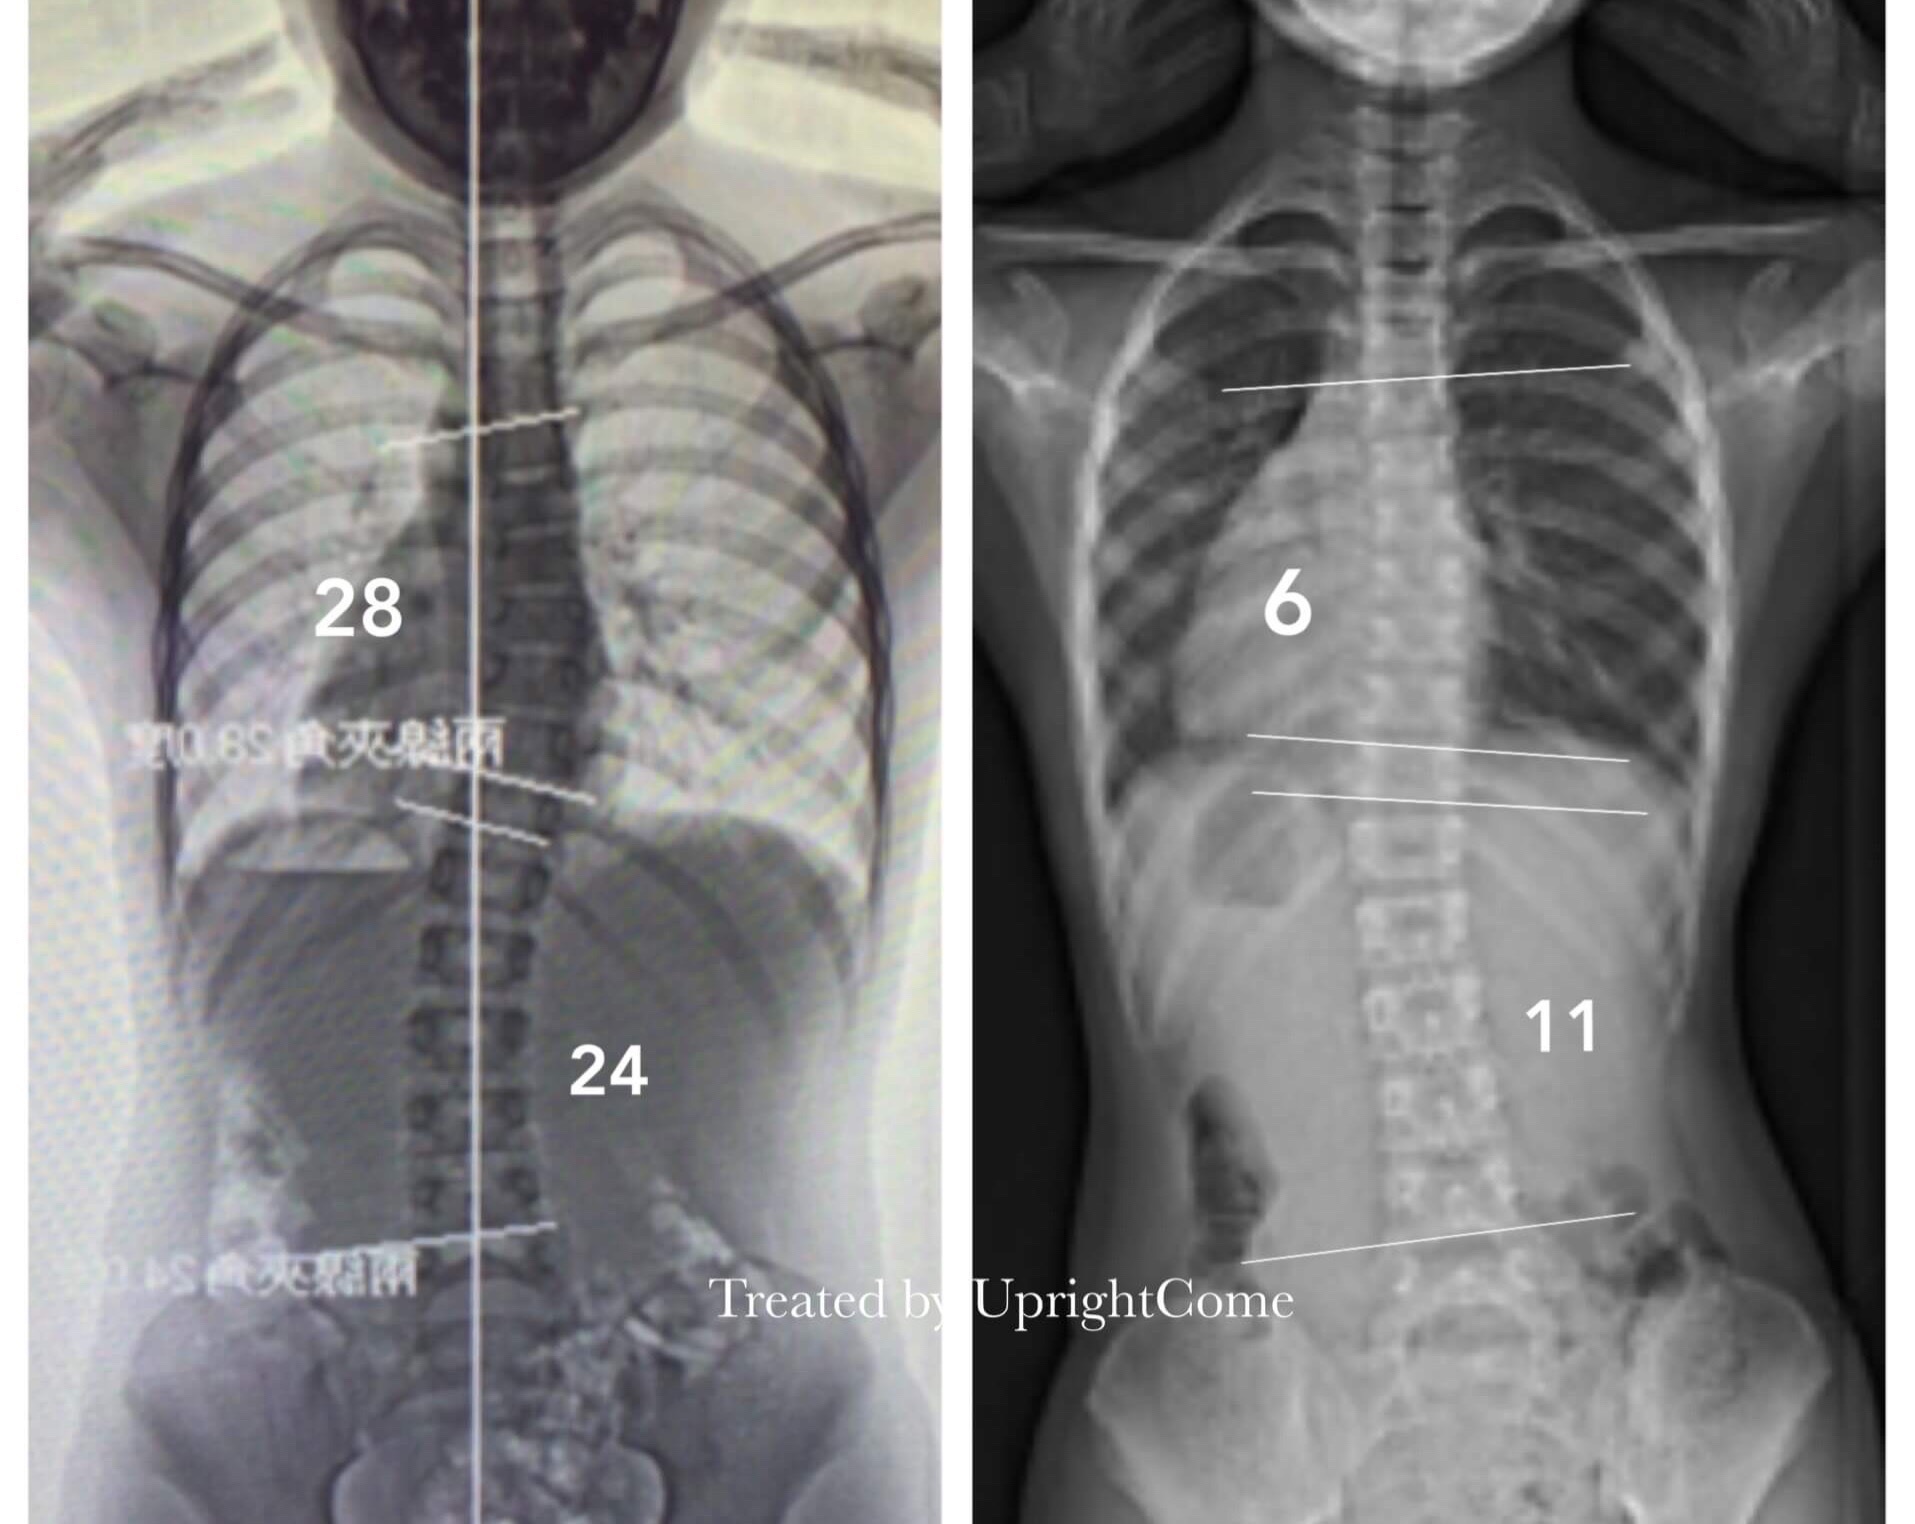

案例 7,10 歲,減少 90%

![脊椎側彎患者經過側彎矯正治療後,胸椎角度由28度減少到6度,腰椎角度由24度減少到11度。]()